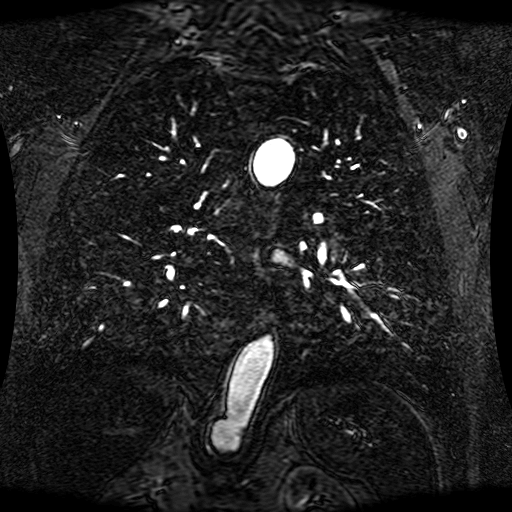

These magnetic resonance angiography (MRA) images show coronal slices acquired from consecutive anteroposterior positions within the torso. The study was performed on a 1.5T General Electric (GE) Signa imaging system with gadolinium-contrast-enhancement for visualization of the cardiopulmonary vasculature. The pulse sequence used was a 3D time-of-flight fast spoiled gradient recalled acquisition in steady state (FSPGR, TR=6.3, TE=1.4, NEX=1, FOV = 40cm, slice thickness = 1.2mm).

This sample image contains 76 frames. It is available in DICOM format (E1154S7I.dcm), as an animated GIF (E1154S7I.gif), as .ogg, .mp4, .webm, and .swf animations (one of which is shown above), or as individual PNG-format frames (see below).